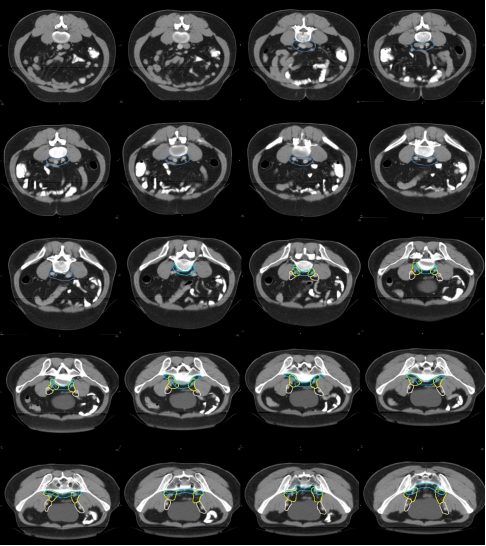

CTV 勾畫示范

a) 骶前區(qū):分為腹部骶前區(qū)和盆腔骶前區(qū)

腹部骶前區(qū)-PS S (青色) (圖 5),邊界:

上界:腹主動脈分叉為左、右髂總動脈處或該區(qū)域內(nèi)轉(zhuǎn)移淋巴結(jié)上方至少 0.5 cm;

下界:骶岬;

前界:腰椎前方 1 cm,髂總血管前 1.0 cm;

后界:腰椎前緣;

外界:髂總血管外側(cè)外 0.7~1.0 cm。

盆腔骶前區(qū)-PS (淡藍(lán)色) (圖 6),邊界:

上界:髂總動脈分叉為髂內(nèi)、外動脈處/骶岬;

下界:肛提肌插入外括約肌處/直腸周圍系膜脂肪組織消失處,相當(dāng)于尾骨尖水平;

前界:腰椎前方 1.0 cm/骶骨尾骨前方 1 cm/直腸系膜筋膜后緣;

后界:腰椎前緣/骶骨尾骨前緣;

外界:骶髂關(guān)節(jié)/髂肌內(nèi)緣。

圖 5 直腸癌腹部骶前區(qū) CTV 勾畫示例

圖 6 直腸癌盆腔骶前區(qū) CTV 勾畫示例

b) 直腸系膜區(qū)-M(深綠) (圖 7),邊界:

上界:腸系膜下動脈分叉為乙狀結(jié)腸動脈與直腸上動脈處/直乙交界;

下界:肛提肌插入外括約肌處/直腸周圍系膜脂肪組織消失處;

前界上:直腸上動脈前緣擴(kuò) 0.7 cm;

前界中/下:直腸系膜筋膜,前方盆腔器官的后界;

后界:盆腔骶前區(qū)的前界;

外界上:側(cè)方、髂外淋巴結(jié)區(qū)的內(nèi)側(cè);

外界中:直腸系膜筋膜,側(cè)方淋巴結(jié)區(qū)的內(nèi)側(cè);

外界下:肛提肌內(nèi)側(cè)緣。

圖 7 直腸癌直腸系膜區(qū) CTV 勾畫示例

c) 髂內(nèi)淋巴引流區(qū)-LLN P(黃色) (圖 8)邊界:

上界:髂總動脈分叉為髂內(nèi)、外動脈處;

下界:肛提肌插入外括約肌處/骨盆底;

前界上:血管外 0.7 cm;

前界中:輸尿管進(jìn)入膀胱的虛擬冠狀平面,髂外血管上段的后方;

前界下:閉孔內(nèi)肌后緣;

后界:骶髂關(guān)節(jié)外側(cè)緣;

內(nèi)界上:血管周圍 0.7 cm(直腸系膜以上),不必避開正常解剖結(jié)構(gòu);

內(nèi)界中/下:直腸系膜筋膜,盆腔器官;

外界上:髂腰肌,骨盆;

外界中/下:盆壁肌肉(梨狀肌和閉孔內(nèi)?。┑膬?nèi)側(cè)緣。

圖 8 直腸癌髂內(nèi)淋巴引流區(qū) CTV 勾畫示例

d) 閉孔淋巴引流區(qū)-LLN A(紫色) (圖 9)邊界:

上界:股骨頭頂;

下界:閉孔動脈離開骨盆層面;

前界中:髂外血管后壁;

前界下:當(dāng)髂外血管離開骨盆或閉孔動脈前緣;

后界:閉孔內(nèi)肌后緣或髂內(nèi)淋巴結(jié)區(qū)前緣;

內(nèi)界:直腸系膜筋膜,盆腔器官;

外界:閉孔內(nèi)肌的內(nèi)側(cè)緣。

圖 9 直腸癌閉孔淋巴引流區(qū) CTV 勾畫示例